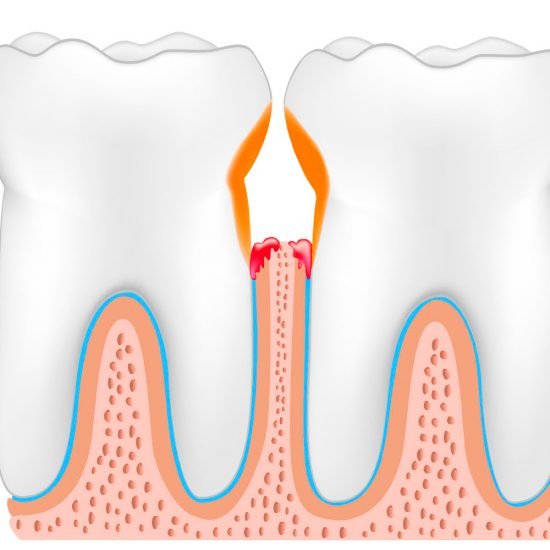

Gengive rosse, gengive gonfie, gengive infiammate, gengive che sanguinano, cattivo sapore in bocca, cattivo odore in bocca, spazi interdentali eccessivi, placca e tartaro abbondanti, sensibilità dentinale, mobilità dentale, perdita di denti sani.

Patologie come la Parodontite, oggi più propriamente definita Malattia Parodontale, sono spesso asintomatiche fino al palesarsi di conseguenze irreversibili.

Non aspettate evidenze irreversibili, quali la mobilità dentale o la formazione di tasche gengivali purulente, rivolgetevi a Noi prima, passate per un controllo. E’ Gratis.